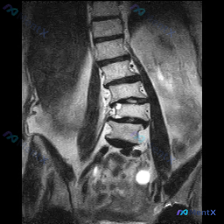

整理到一份腰椎MRI T2加权序列冠状位的影像分析,有几个点挺值得讨论的: 1. 冠状面上能看到腰椎明显向右侧弯,脊柱中心轴线偏移 2. L2/L3、L3/L4、L4/L5椎间隙不均匀,尤其是下腰段有左右不对称的压缩倾向 3. 椎体边缘有骨质增生(骨赘),下腰段多个椎间盘T2信号减低("黑盘"征)...

整理到一份腰椎MRI-T2冠状位的影像资料,第一眼就能看到明确的脊柱侧弯——腰椎呈C型向左侧凸。 但仔细看还有几个点: 1. 侧弯凸侧(右侧)椎体边缘有不同程度骨赘形成 2. 双侧小关节增生明显,关节周围有高信号 3. 椎间隙左右不对称,凹侧(左侧)椎间孔空间看起来受压缩 4. 目前层面没看到明确的...